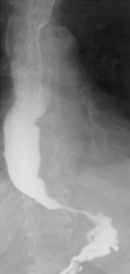

Barium swallow. Red arrow — previous Nissen fundoplication. Yellow arrow — narrowed distal esophagus with tapering of its terminal segment. Green outline — right paraesophageal hiatal hernia (Courtesy Dr. V. Penopoulos)